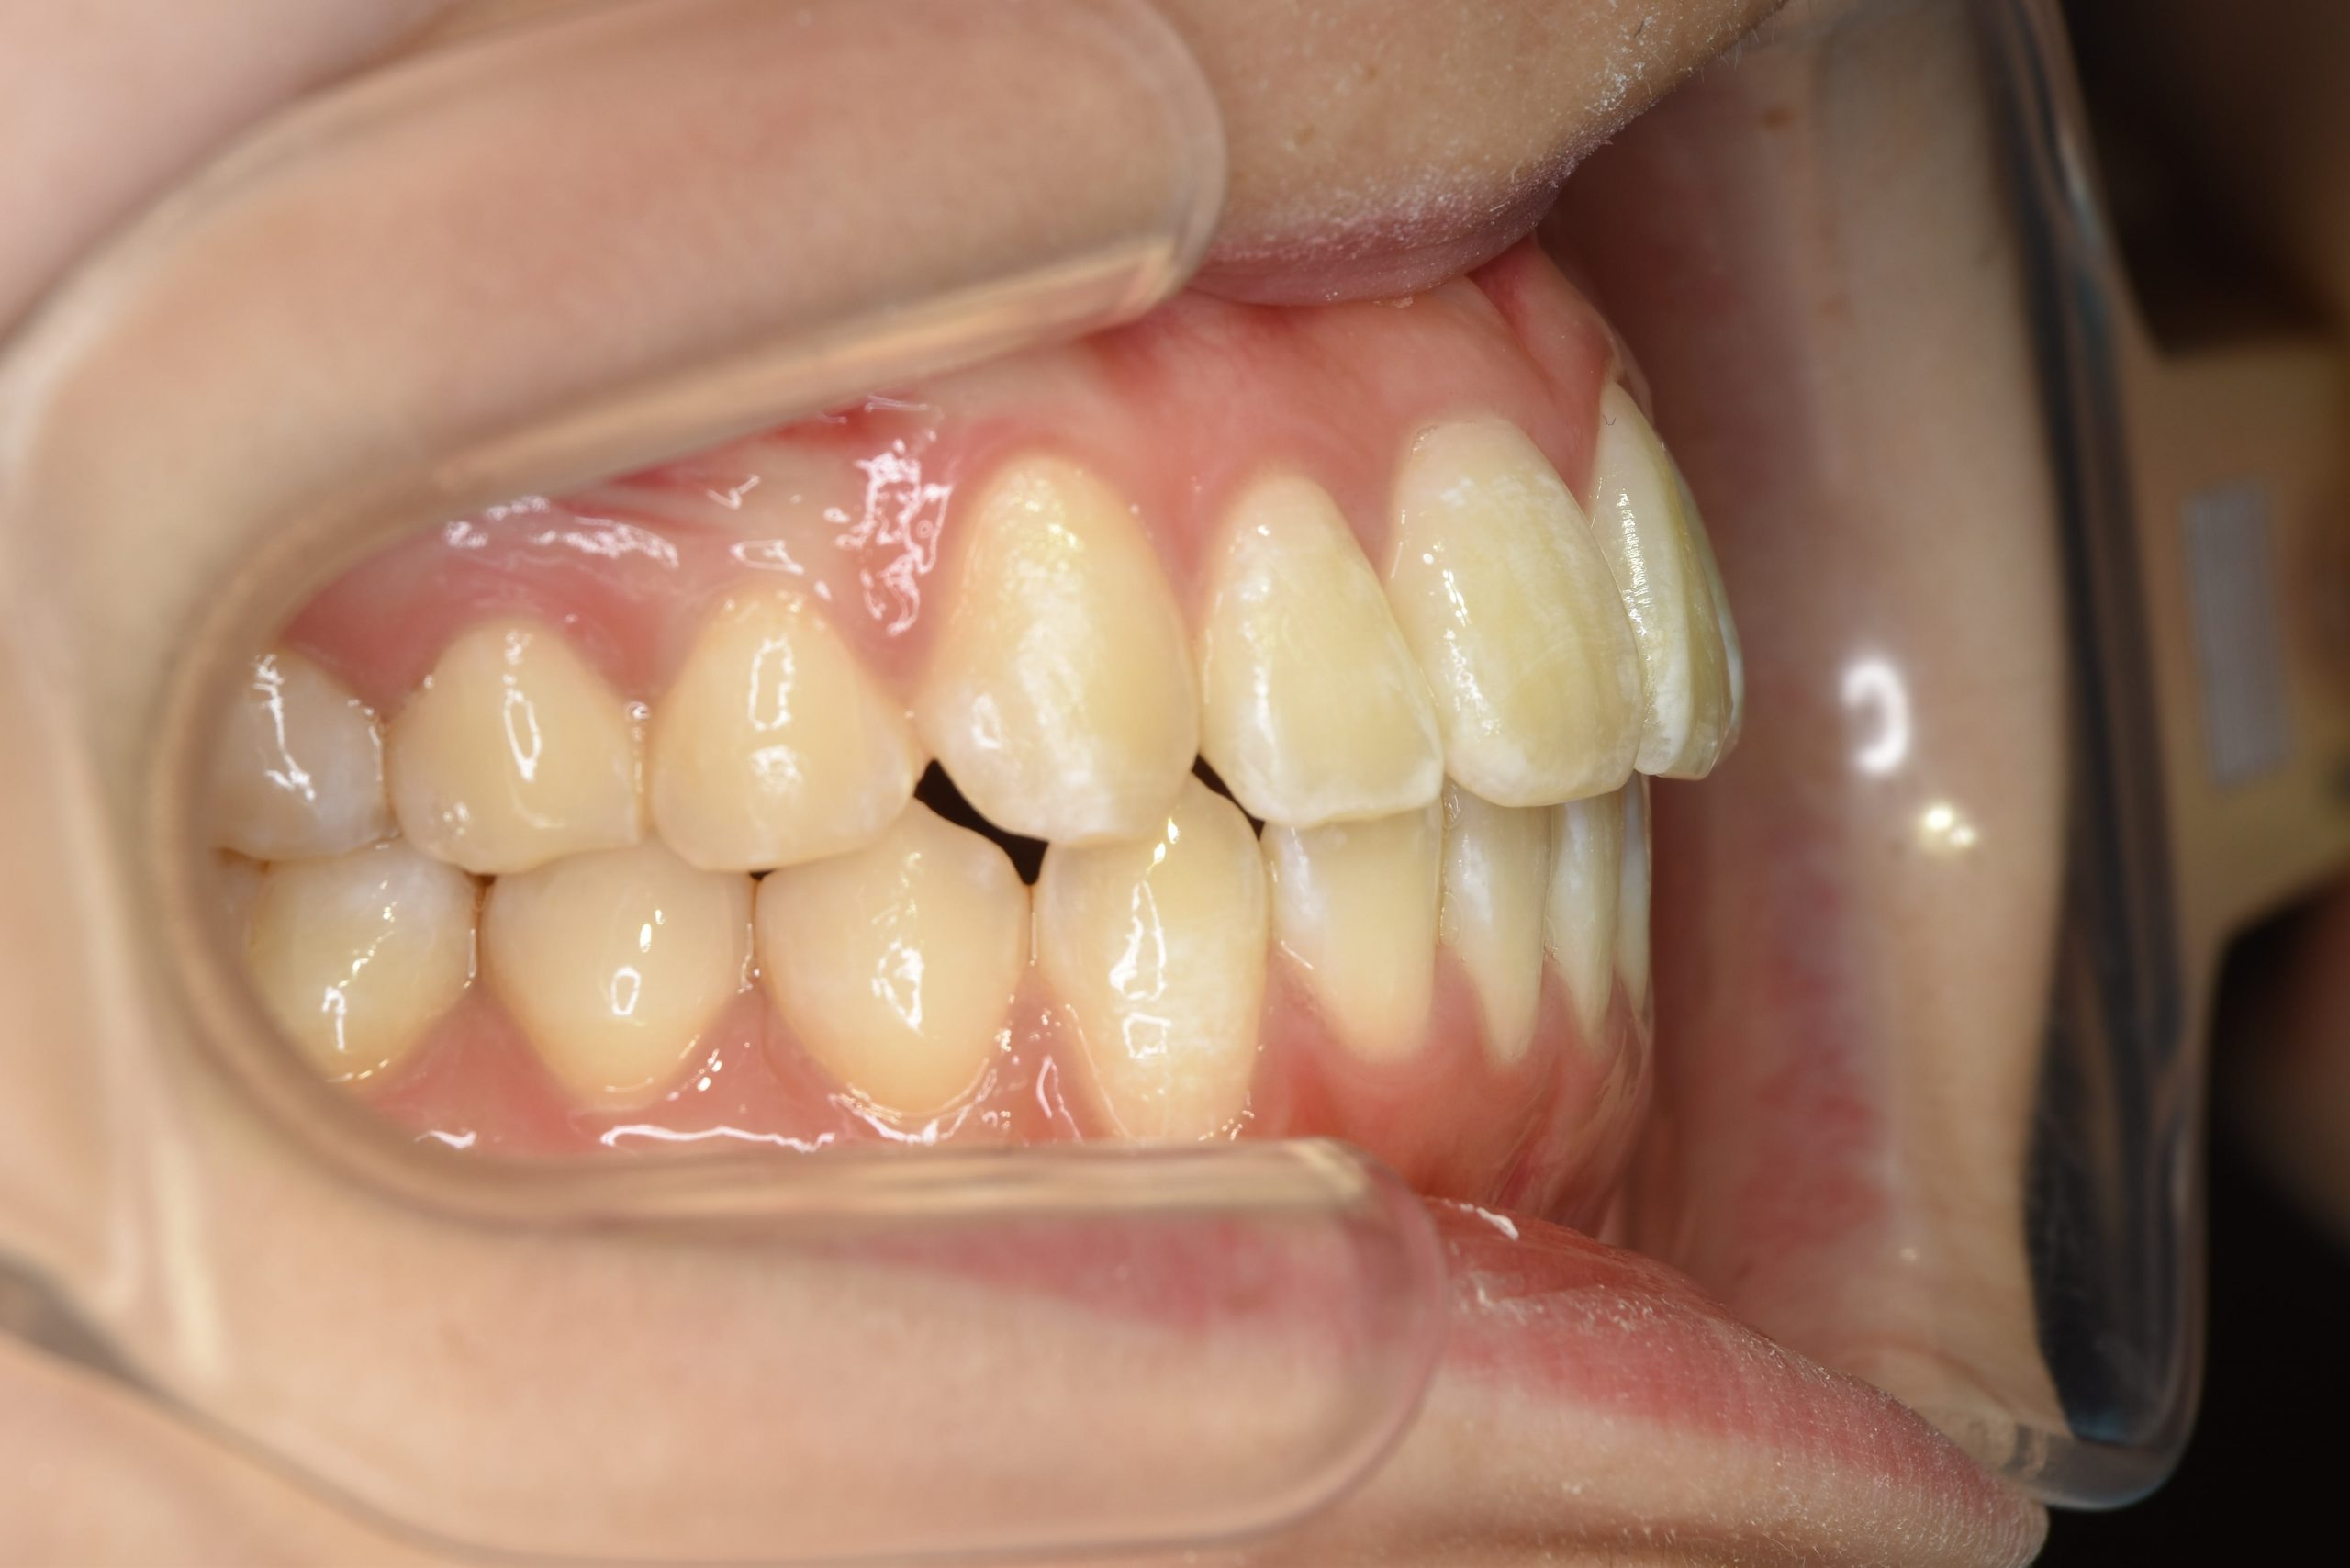

ビフォー

主訴 前歯の出っ歯|八重歯|下の歯のデコボコ|検診で噛み合わせが悪いと指摘されたこと

施術内容 成人矯正1期治療

治癒期間 1年4か月間

費用 954,800円(税込)

リスク・副作用 違和感、不快感、痛み